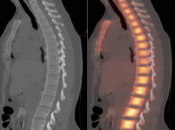

Normal Skeletal Uptake

Mild to moderate FDG uptake can be normally seen within red marrow, most commonly affecting the vertebral bodies, sternum, pelvis, and proximal long bones (it is not unusual to see fairly prominent uptake within the proximal half of the femurs). This red marrow uptake can be quite heterogeneous at times, yet still normal.

Diffuse Skeletal Uptake:

Intense and diffuse reactive marrow uptake is frequently seen as the result of chemotherapy and/or colony stimulating factors (discussed in detail, here).

If rather diffuse and intense uptake is noted without a history of recent chemotherapy or colony stimulating factors, be suspicious of infiltrating disease such as lymphoma.